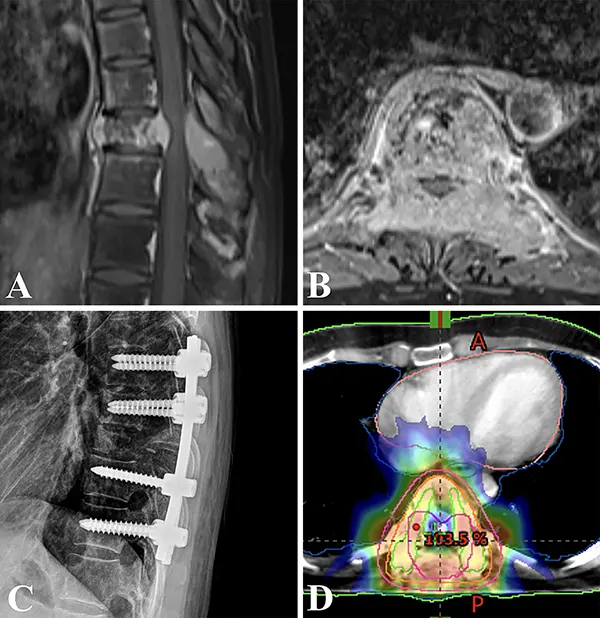

ხერხემლის ჩვეულებრივი რენტგენოგრაფიის დროს შეიძლება გამოჩნდეს მალის სხეულის განადგურება ან კომპრესიული მოტეხილობა ზურგის ტვინის დაზიანების სინდრომის შესაბამის დონეზე. უფრო მეტ ინფორმაციას გვაძლევს ძვლოვანი ქსოვილის სცინტიგრაფია. ყველაზე მეტ მონაცემს კი ზურგის ტვინის კომპრესიის შესახებ გვაძლევს მისი გამოკვლევა კომპიუტერულ ტომოგრაფიაზე, მაგნიტურ-რეზონანსულ ტომოგრაფიასა და მიელოგრაფიაზე (კონტრასტირებით). ჰორიზონტალური სიმეტრიული გაფართოების უბანი და ზურგის ტვინის ექსტრამედულარული პათოლოგიური წარმონაქმნით კომპრიმირებული ზეწოლა ჩანს სუბარაქნოიდული სივრცის ბლოკადის (ლიკვორული ბლოკის) კიდეებზე. ლიკვორული ბლოკის დროს პაციენტს უვლინდება ცვლილებები მეზობელი მალების მხრიდანაც.

სისმსივნური ზურგის ტვინის ექსტრამედულარული ზეწოლის დროს სამკურნალო ტაქტიკა შეიძლება იყოს კონსერვატიული და ოპერატიული. ნეიროქირურგიულ სტაციონარში სიმსივნური ზურგის ტვინის ექსტრამედულარული კომპრესიის მქონე პაციენტს შეიძლება ჩაუტარდეს ოპერაცია ლამინექტომია. ეს ოპერაცია აფართოებს ძვლოვან ფანჯარას სიმსივნური მასებით კომპრესირებულ ზურგის ტვინის უბანზე. მკურნალობის კონსერვატიული მეთოდის დროს ზურგის ტვინის ექსტრამედულარული ზეწოლის მქონე პაციენტებში იყენებენ კორტიკოსტეროიდების დიდ დოზებს ფრაქციული სხივური თერაპიის თანხლებით. მკურნალობის ასეთი მეთოდის შედეგი დამოკიდებულია სიმსივნის ტიპზე და მის მგრძნობელობაზე სხივური თერაპიის მიმართ. ორი დღე-ღამის განმავლობაში კორტიკოსტეროიდების შეყვანის შემდეგ ავადმყოფებს ფეხის კუნთების სისუსტის (პარაპარეზის) გამოხატულობა უმცირდებათ. ზურგის ტვინის განივი დაზიანების ზოგი არასრული ადრეული სინდრომის გამოვლენის დროს მიზანშეწონილი შეიძლება იყოს ნეიროქირურგიული მკურნალობა. ნებისმიერ შემთხვევაში საჭიროა მკურნალობის ტაქტიკის ინდივიდუალური ანალიზი სიმსივნის რადიომგრძნობელობის, სხვა მეტასტაზების ადგილმდებარეობისა და ავადმყოფის საერთო მდგომარეობის გათვალისწინებით. მკურნალობის შერჩეული ტაქტიკა (ოპერაციული მკურნალობა, სხივური თერაპია) პაციენტს სწრაფად უნდა ჩაუტარდეს. თუ ეჭვი აქვთ ზურგის ტვინის ზეწოლაზე (სპინალურ კომპრესიაზე), ინიშნება კორტიკოსტეროიდები.

ოპერაციის დროში გადავადება და ხერხემლის გულმკერდის ნაწილის დაზიანება დამამძიმებელი პროგნოზული ფაქტორებია ზურგის ტვინის ეპიდურული მეტასტაზური შეკუმშვის მქონე პაციენტის ნევროლოგიური აღდგენისთვის. გარდა ამისა, ოპერაციის წინ უფრო გამოხატული ნევროლოგიური დეფიციტი დაკავშირებული არის ოპერაციის შემდეგ სიარულის ფუნქციის სრული აღდგენის დაბალ ალბათობასთან. მოძრაობის დარღვევების ადრეული გამოვლენა და დროული ქირურგიული ჩარევა აუცილებელია არა მხოლოდ პაციენტის ფუნქციური მდგომარეობისა და ცხოვრების ხარისხის გასაუმჯობესებლად, არამედ მისი გადარჩენის გაზრდის მიზნით.